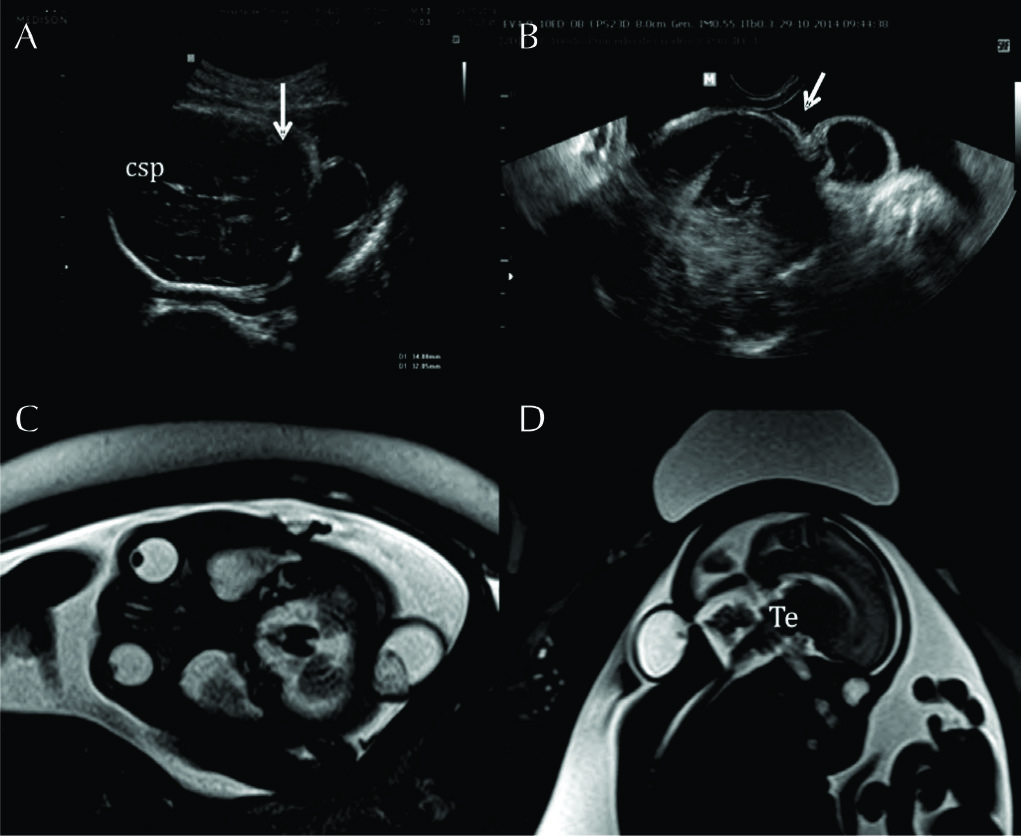

Figura 13

Correlación entre NSF y RMf en malformaciones.

Correlación entre hallazgos ecográficos y RMf en un feto con estudio ecográfico por via abdominal (A) y trans-vaginal (NSF) (B). Se observa solución de continuidad a nivel de la región occipital con contenido meníngeo, sin herniación de parénquima encefálic,o (è). Esto se confirma mediante RMf (C) corte axial; D: corte sagital) lo que establece el diagnóstico de meningocele occipital. CSP: cavum septum pellucidum

V: vermis cerebeloso

Te: tronco encefálico